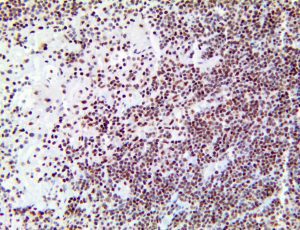

It is the ICU physician who is most likely to witness one of the deadliest manifestations of the abnormal immunological response, the cytokine storm syndrome (CSS). This response is also referred to by some as the cytokine release syndrome (CRS). CSS is characterized by continuous activation and expansion of macrophage and lymphocyte populations, which secrete large amounts of cytokines, causing the cytokine storm. This massive cytokine release is akin to hemophagocytic lymphohistiocytosis (HLH) disease, a syndrome characterized by initial unchecked and persistent activation of cytotoxic T lymphocytes and NK cells.

Clinical and laboratory manifestations of HLH include fever, enlarged liver and/or spleen, neurologic dysfunction, coagulopathy, liver dysfunction, cytopenias (i.e., low levels of erythrocytes, leukocytes, and/or platelets), hypertriglyceridemia, hyperferritinemia, hemophagocytosis, and eventually diminished NK cell activity as the immune system becomes progressively paralyzed. HLH can be familial (primary HLH) or secondary to another disease process (sHLH), such as rheumatic disease, in which it is referred to as macrophage activation syndrome (MAS, characterized by elevated ferritin).